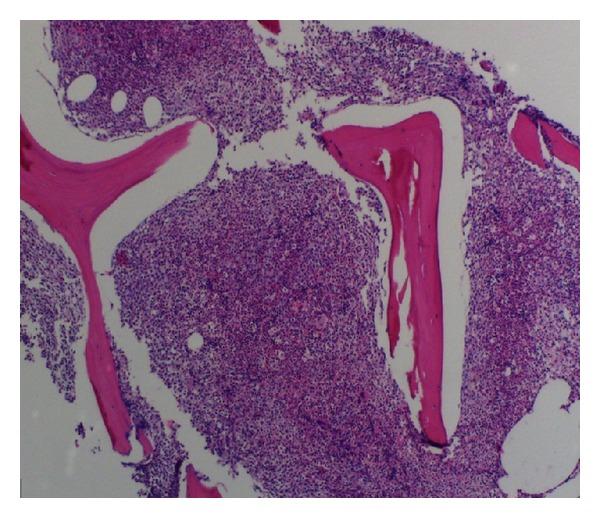

A 63-year-old female was incidentally found to have leukocytosis and referred to the hematology service for evaluation. Complete blood count (CBC) revealed neutrophilia with band predominance and mild thrombocytopenia. Peripheral blood flow cytometry was unremarkable without any evidence of lymphoproliferative disorder or myeloblasts. Bone marrow aspiration and biopsy revealed a markedly hypercellular marrow with myeloid lineage predominance and approximately 10% plasma cells. The monoclonal gammopathy was determined as lambda light chain with a kappa/lambda ratio of 0.06. Cytogenetics revealed normal karyotype, JAK2 kinase was negative, and rearrangement of BCR-ABL1, PDGFRA, PDGFRB, and FGFR1 was negative. The patient was diagnosed with chronic neutrophilic leukemia (CNL) associated with light chain multiple myeloma, complicated by a subdural hemorrhage. She was treated with hydroxyurea and bortezomib/dexamethasone and had complete response with normalization of CBC and kappa/lambda ratio. To the best of our knowledge, we report the first case of chronic neutrophilic leukemia and multiple myeloma treated with bortezomib/dexamethasone.

一名63岁女性偶然发现白细胞增多,遂转诊至血液科进行评估。全血细胞计数(CBC)显示中性粒细胞增多伴杆状核为主,以及轻度血小板减少。外周血流式细胞术未见异常,无任何淋巴细胞增殖性疾病或原始粒细胞的证据。骨髓穿刺和活检显示骨髓明显细胞增多,以髓系为主,约10%浆细胞。单克隆丙种球蛋白病确定为λ轻链,κ/λ比值为0.06。细胞遗传学显示核型正常,JAK2激酶阴性,BCR-ABL1、PDGFRA、PDGFRB和FGFR1重排均为阴性。该患者被诊断为慢性中性粒细胞白血病(CNL)合并轻链多发性骨髓瘤,并发硬膜下出血。她接受了羟基脲和硼替佐米/地塞米松治疗,CBC和κ/λ比值恢复正常,达到完全缓解。据我们所知,我们报告了首例用硼替佐米/地塞米松治疗的慢性中性粒细胞白血病和多发性骨髓瘤病例。